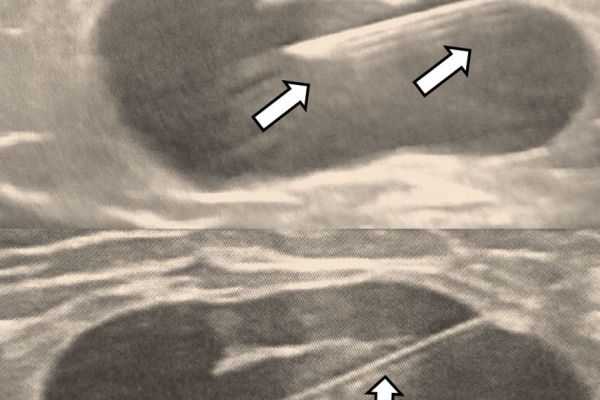

Η διαδερμική βιοψία είναι μία ελάχιστα επεμβατική μέθοδος λήψης υλικού από τον όγκο για κυτταρολογική και ιστολογική εξέταση, από εστιακές αλλοιώσεις του ήπατος, πνεύμονα, νεφρού κλπ. Συστήνεται από τον κλινικό ιατρό ανάλογα με το είδος και το μέγεθος της βλάβης και πραγματοποιείται με ασφάλεια από επεμβατικό ακτινολόγο με την καθοδήγηση αξονικού τομογράφου ή υπερήχων. Στη σύγχρονη ογκολογική θεραπεία όπου γίνεται προσπάθεια καταπολέμησης του καρκίνου σε μοριακό επίπεδο κρίνεται αναγκαία η ακριβής ιστολογική ταυτοποίηση του όγκου ώστε να εφαρμοσθεί εξατομικευμένη θεραπεία για το βέλτιστο αποτέλεσμα. Οι κατευθυνόμενες βιοψίες στοχευουν στο να παρέχουν στον κλινικό ογκολόγο το απαραίτο ιστοπαθολογικό υλικό που θα του επιτρέψει να εφαρμόσει την κατάλληλη θεραπεία για τον ογκολογικό ασθενή.